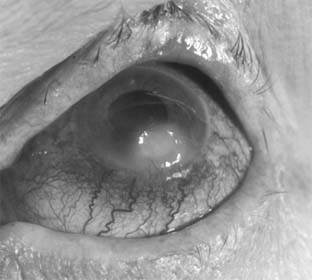

Pneumococcal corneal ulcer usually occurs 24-48 hours after inoculation of an abraded cornea. It typically produces a gray, fairly well circumscribed ulcer that tends to spread erratically from the original site of infection toward the center of the cornea (Figure 6-1). The advancing border shows active ulceration and infiltration as the trailing border begins to heal. (This creeping effect suggested the term "acute serpiginous ulcer.") The superficial corneal layers become involved first and then the deep parenchyma. The cornea surrounding the ulcer is often clear. Hypopyon is common. Scrapings from the leading edge of a pneumococcal corneal ulcer usually contain gram-positive lancet-shaped diplococci. Drugs recommended for use in treatment are listed in Tables 6-2 and 6-3. Concurrent dacryocystitis should also be treated.

Figure 6-1

Figure 6-1: Pneumococcal corneal ulcer with hypopyon.